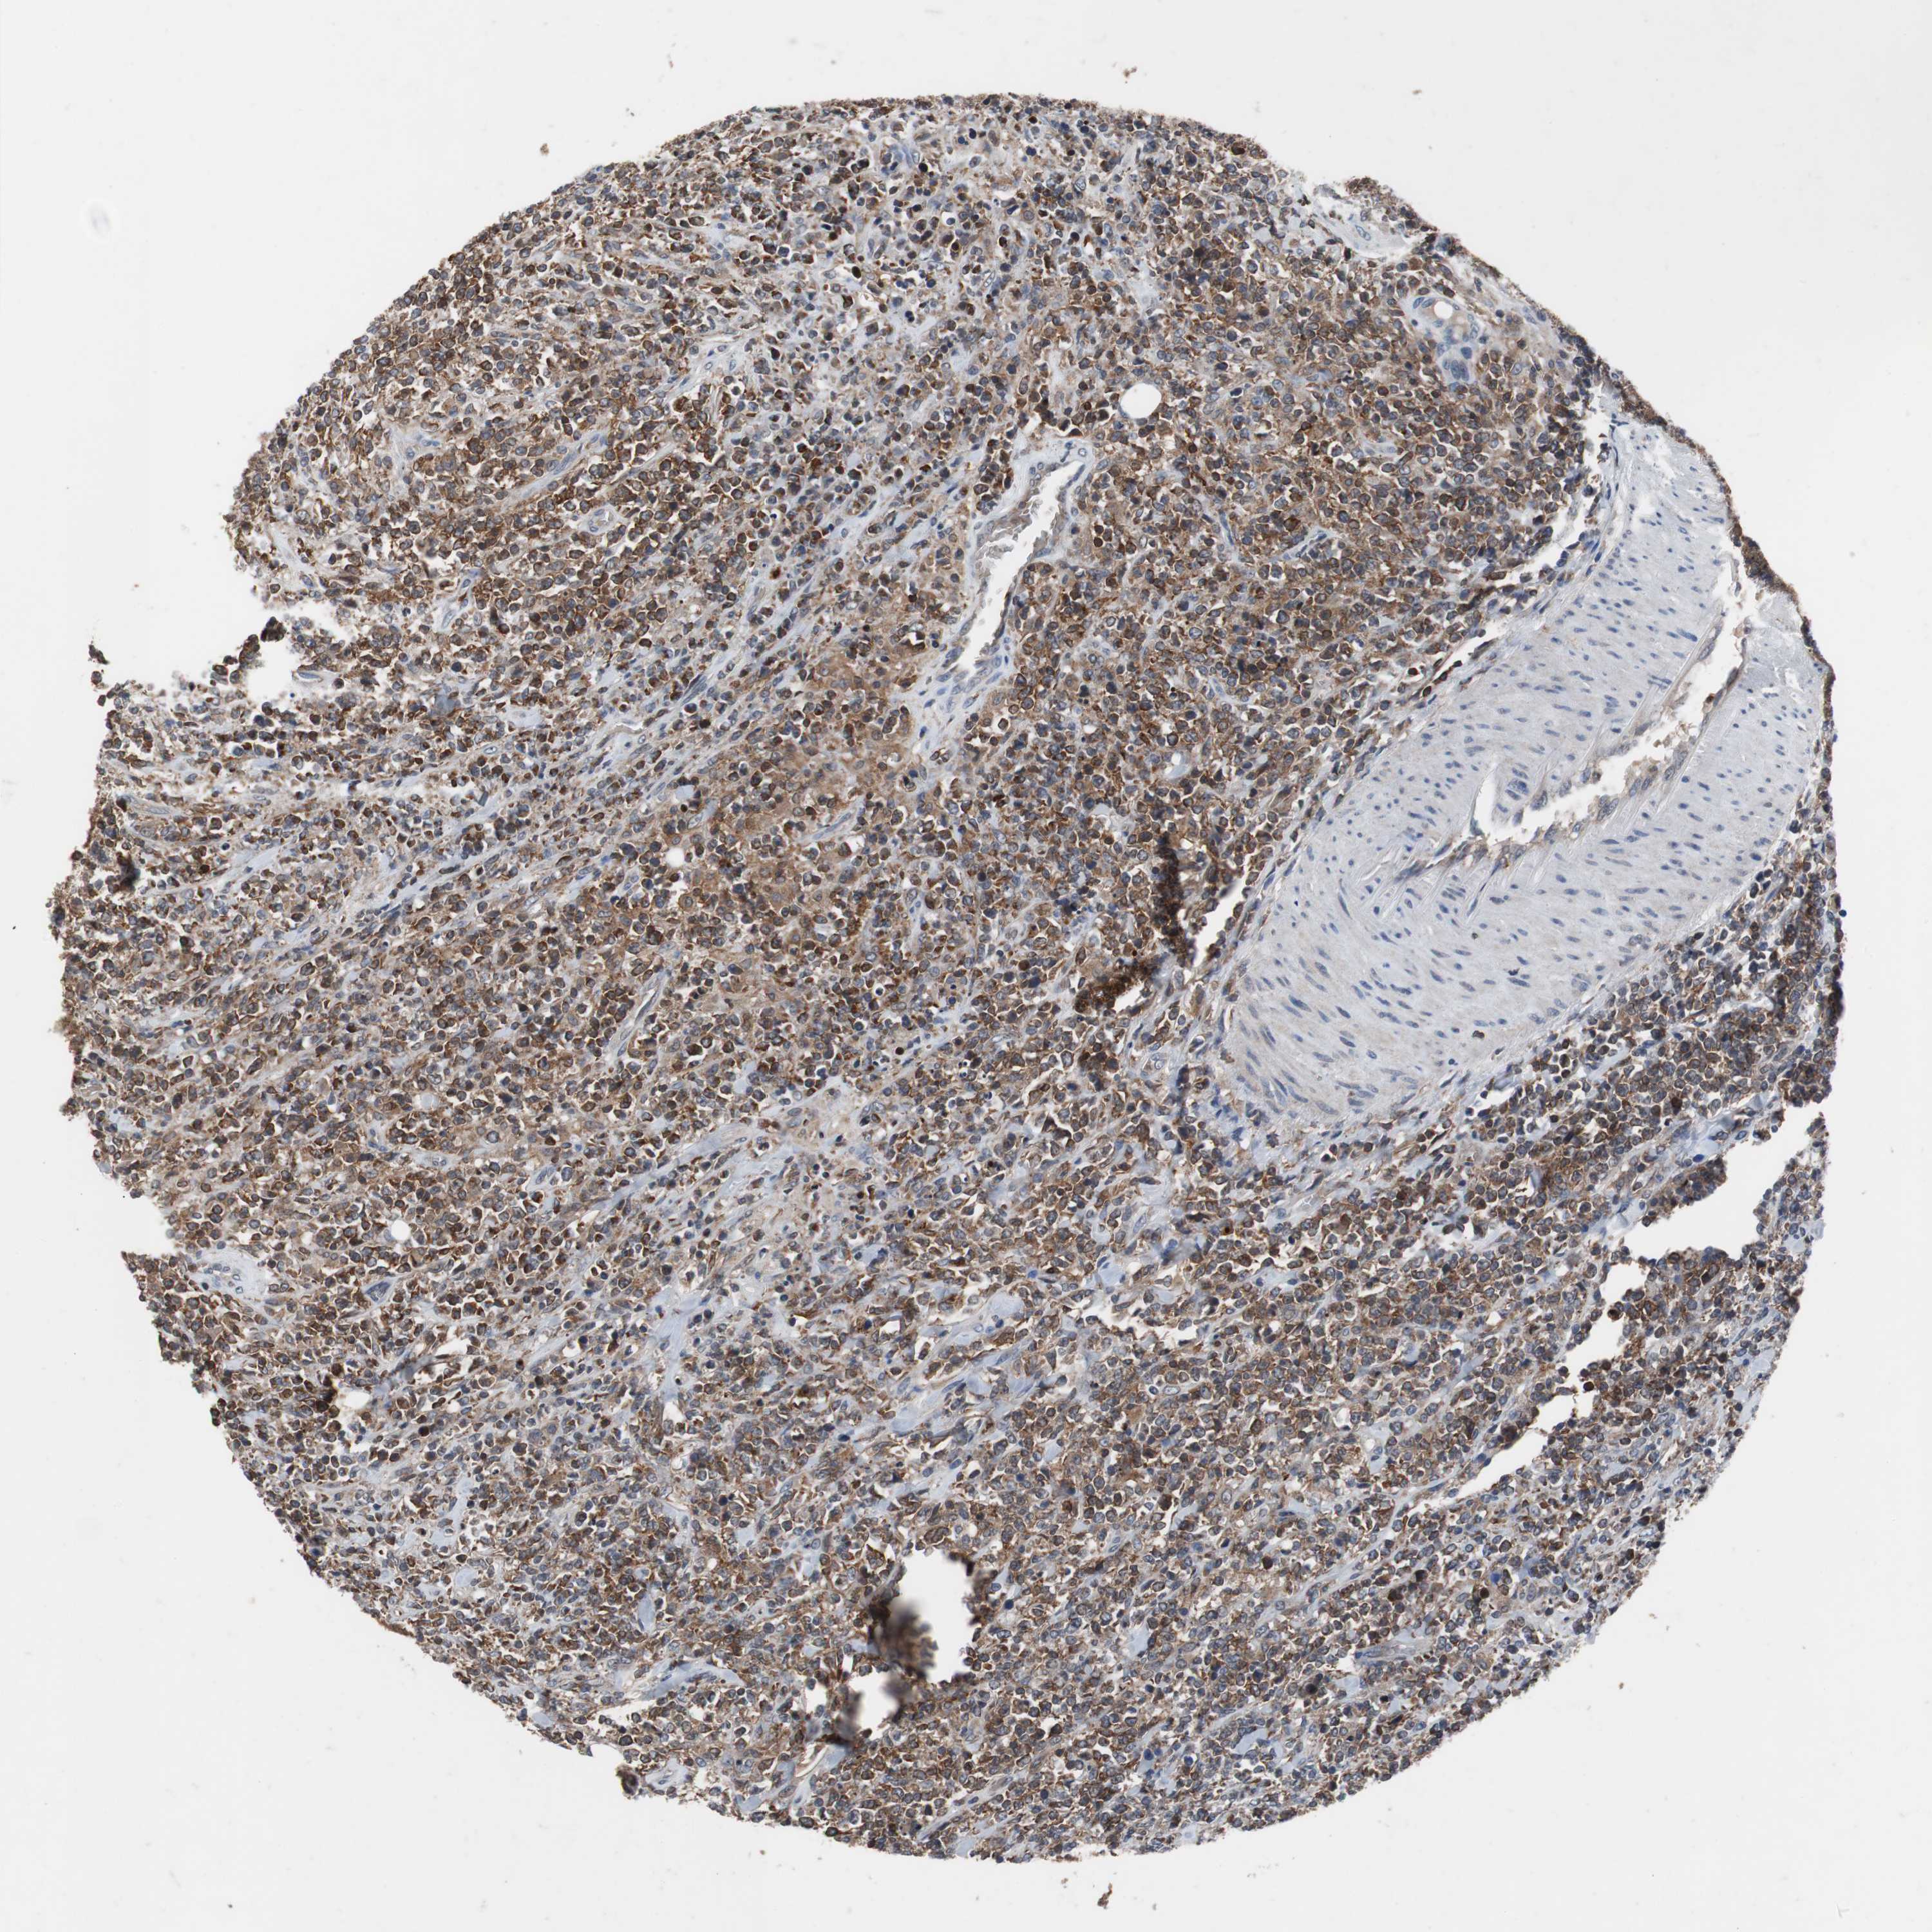

LYMPHOMA - Protein expressioni

A mouse-over function shows sample information and annotation data. Click on an image to view it in a full screen mode. Samples can be filtered based on level of antibody staining by selecting one or several of the following categories: high, medium, low and not detected. The assay and annotation is described here.

Antibody HPA007305

Staining

High

Strong

>75%

Nuclear

Malignant lymphoma, non-Hodgkin's type, High grade